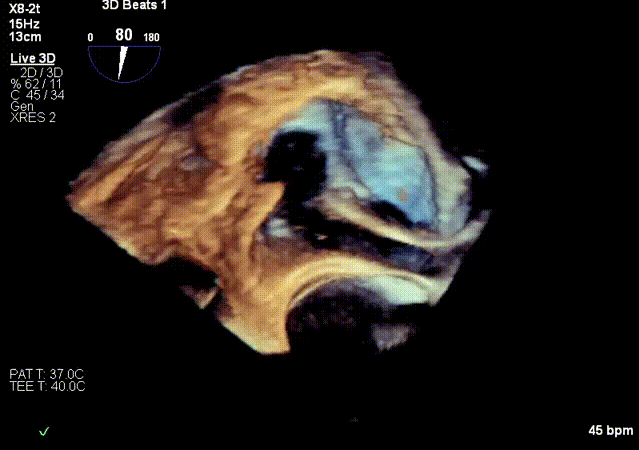

超声基线

2.超声X-Plane以及实时3D下观察输送系统头端指向目标靶位。

实时3D